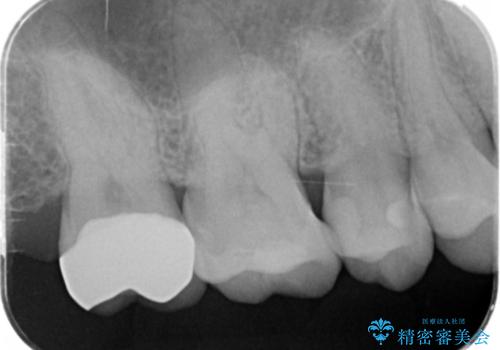

- 20.9万円(ジルコニアクラウン・仮歯・セラミックインレー)費用は治療当時の料金となります

天然歯と変わらない色調に優れるセラミック治療の仕上がりに満足いただくことができました。